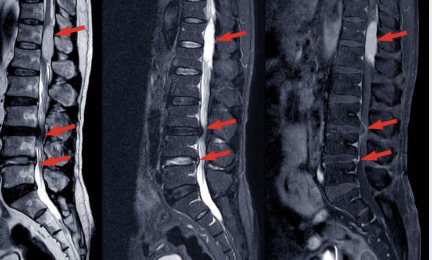

2. 디스크 문제와 신경 압박

허리 디스크가 돌출되거나 손상될 경우 주변 신경을 압박하여 저림이나 통증을 유발할 수 있습니다. 허리 디스크는 척추뼈 사이에 있는 물렁한 조직으로, 충격을 흡수하는 역할을 합니다. 하지만 장기간 잘못된 자세나 무리한 운동으로 인해 디스크가 돌출되면 허리뿐만 아니라 다리까지 저리는 증상이 나타날 수 있습니다. 특히 40대 이상에서 퇴행성 변화로 인해 디스크 문제가 발생하기 쉬운데요, 주기적인 체크와 치료가 필요합니다.

3. 척추 협착증

척추 협착증은 척추관이 좁아져 신경을 압박하는 질환으로, 주로 허리와 다리에 저림 증상을 유발합니다. 협착증은 주로 노화로 인해 발생하지만, 허리에 무리가 가는 활동이 반복될 때도 증상이 나타날 수 있습니다. 최근 연구에 따르면 50대 이상의 연령층에서 협착증 진단율이 높아지고 있으며, 특히 오래 앉아있거나 무거운 물건을 자주 드는 생활습관이 위험 요인으로 작용할 수 있다고 합니다.